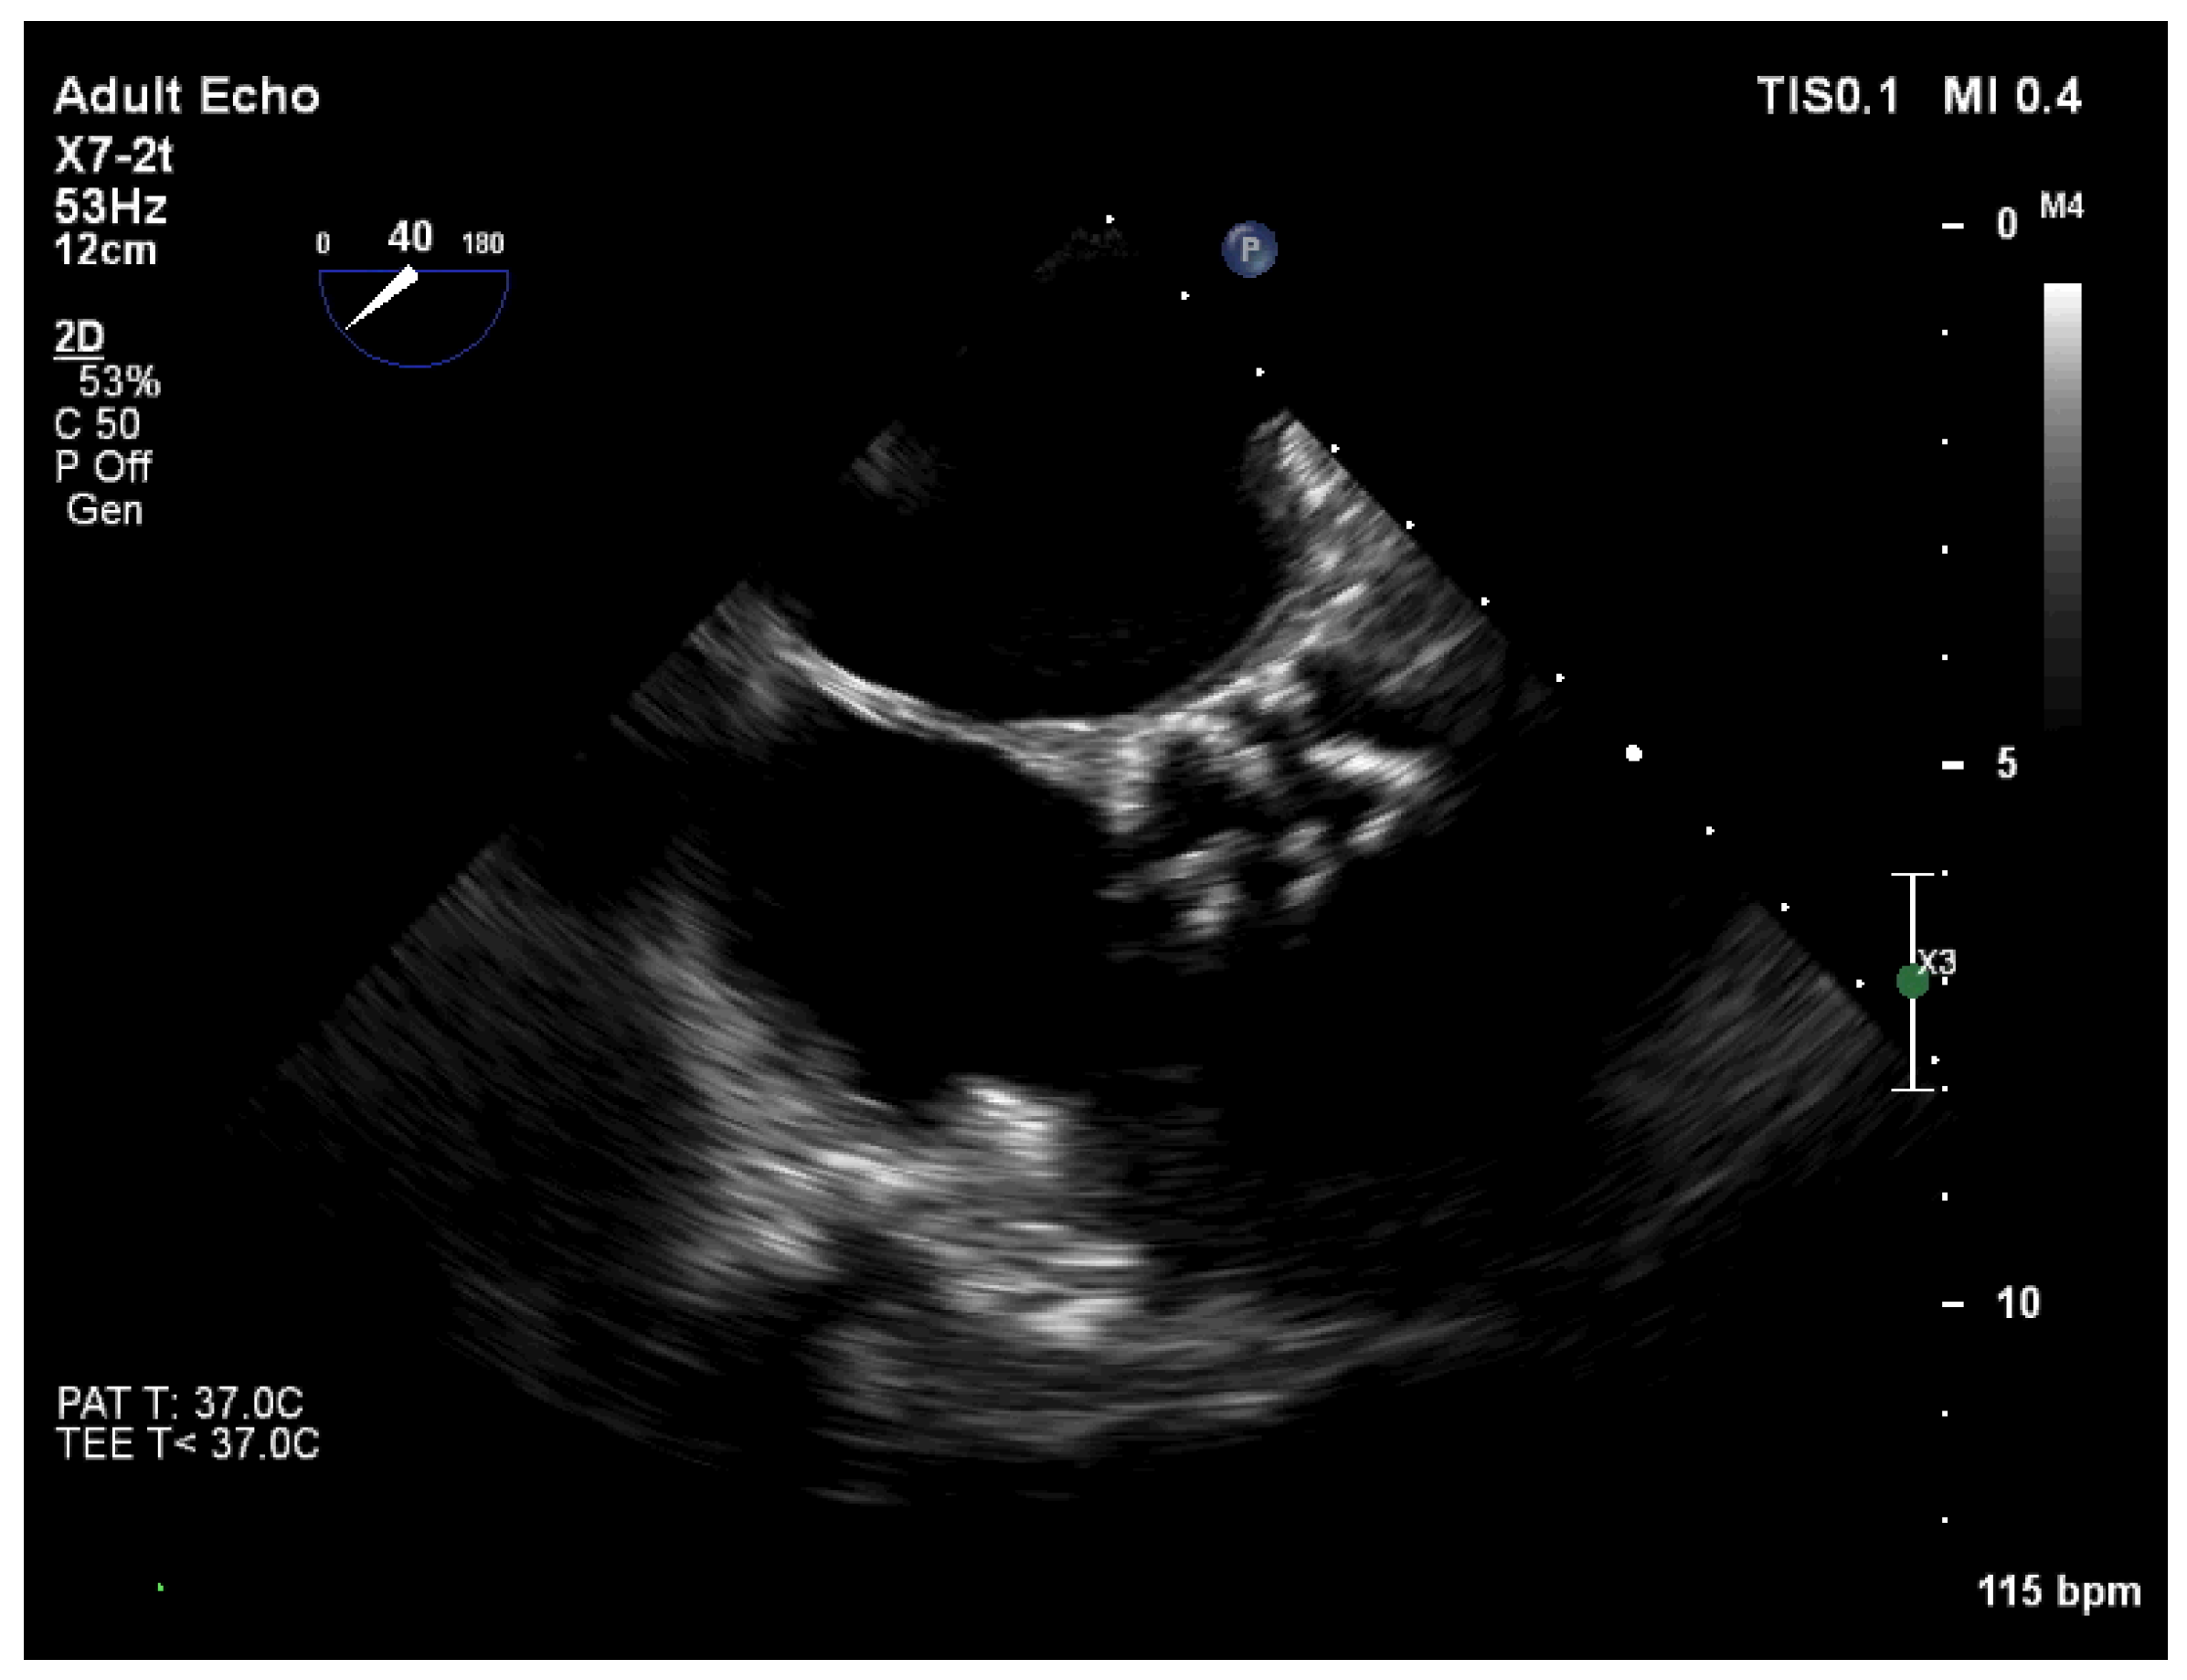

Transthoracic echocardiography (TTE) demonstrated fibrocalcinosis of aortic root, aortic valve annulus, aortic valve cusps (Figure 2a) and moderate to severe aortic stenosis (Vmax 3.36 m/s, Gmean27 mmHg) (Figure 2b), decreased left ventricular (LV) systolic function (ejection fraction 35%), thickened, fibrotic pericardium. In the presence of right ventricular (RV) pressure overload, the interventricular septum shifted towards the LV.

Figure 2. (a) Transthoracic echocardiography demonstrated fibrocalcinosis of aortic root, aortic valve annulus, aortic valve cusps and pericardium; (b) Peak velocity through aortic valve 3.36 m/s, mean gradient through aortic valve—27.39 mmHg.